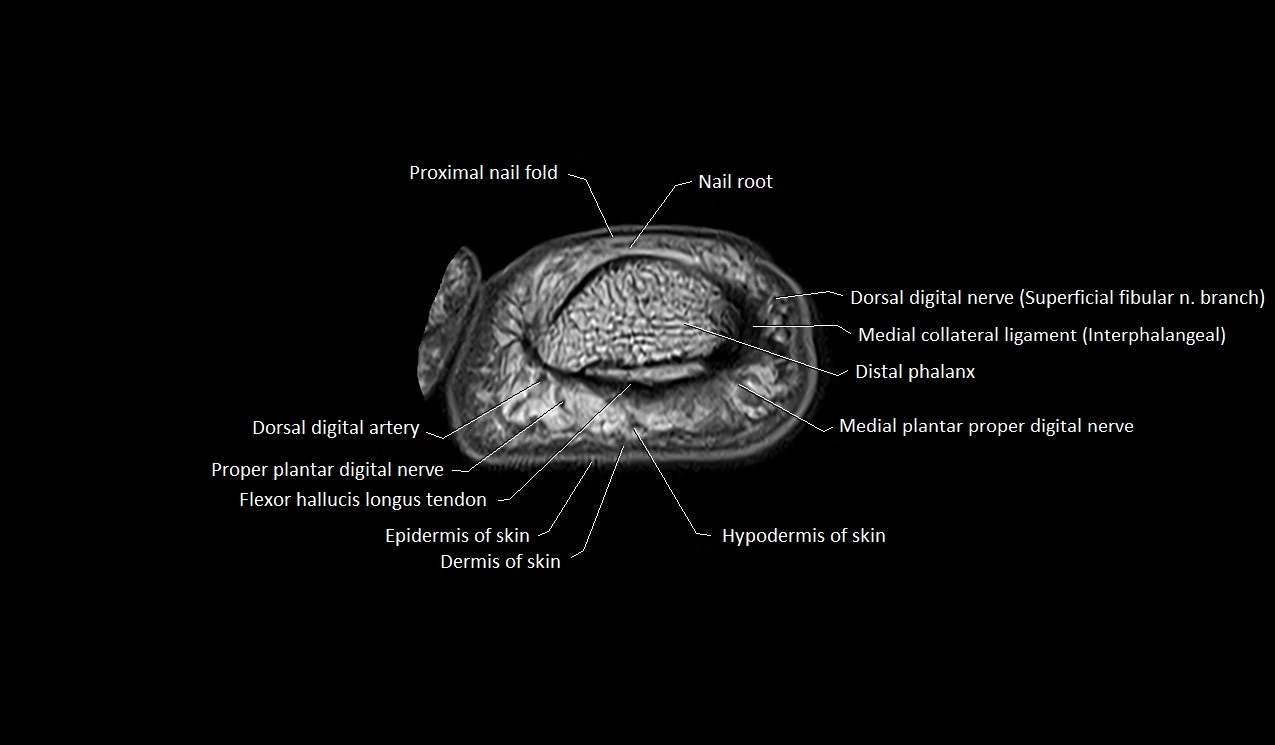

MRI image

image